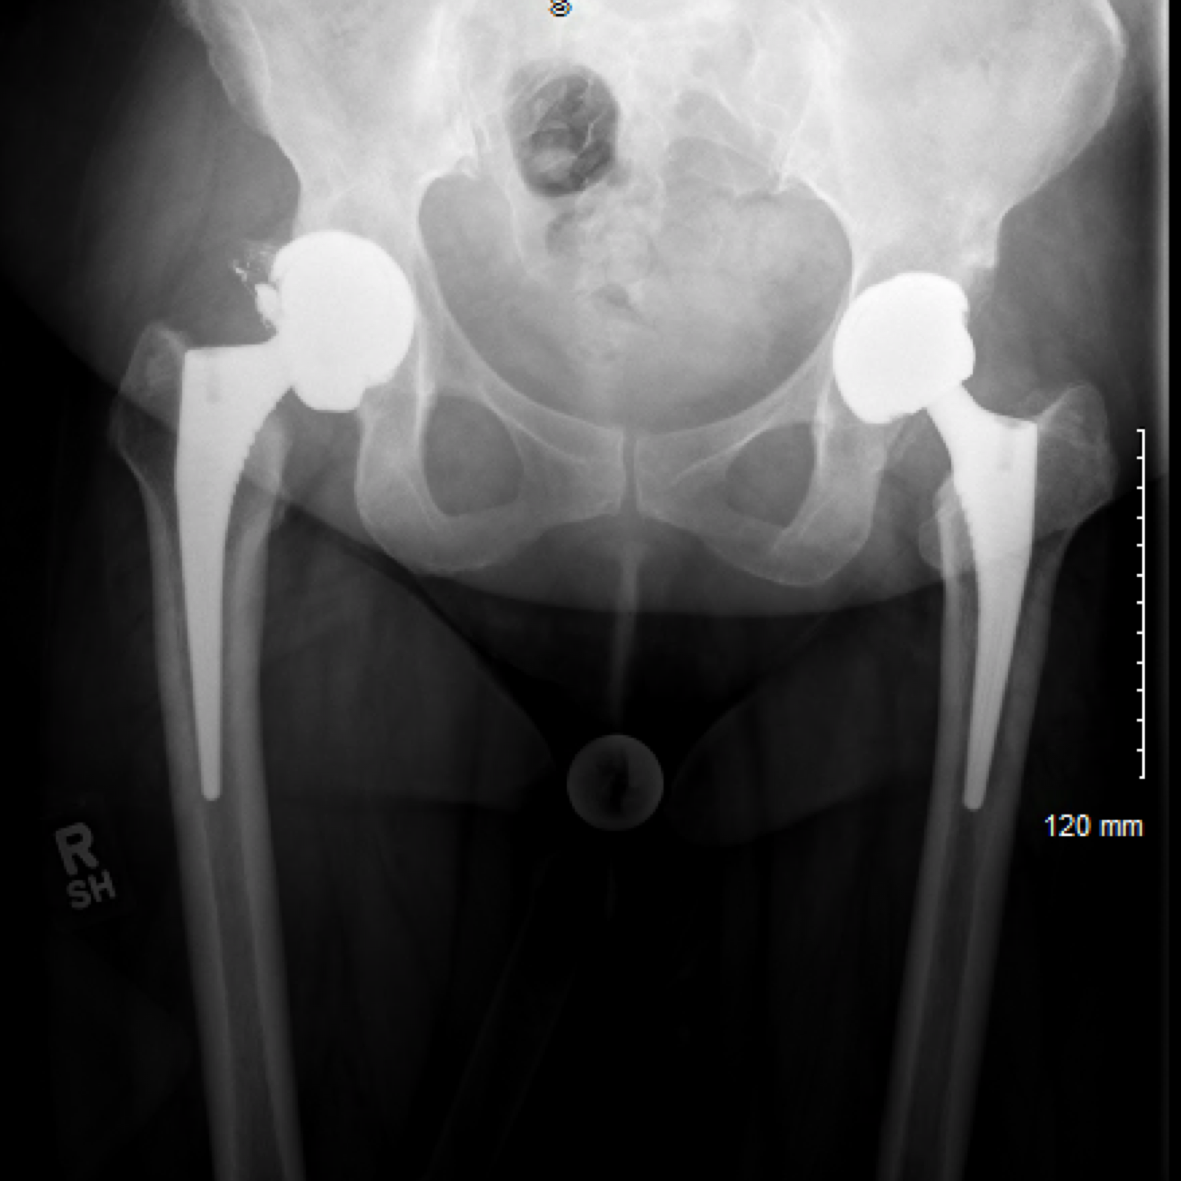

Ceramic Liner Fracture Case Two Complex Hip Surgery